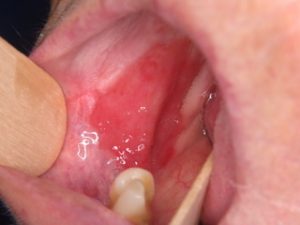

Uma área avermelhada na mucosa bucal, frequentemente associada a um risco mais alto de malignidade em comparação com a manchas brancas